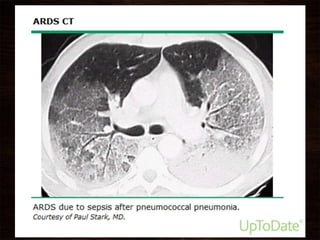

• #40  In addition, condensed plasma proteins aggregate in the air spaces with cellular debris and dysfunctional pulmonary surfactant to form hyaline membrane whorls. Pulmonary vascular injury also occurs early in ARDS, with vascular obliteration by microthrombi and fibrocellular proliferation (Fig. 322-3). Alveolar edema predominantly involves dependent portions of the lung, with diminished aeration and atelectasis. Collapse of large sections of dependent lung markedly decreases lung compliance. Consequently, intrapulmonary shunting and hypoxemia develop and the work of breathing increases, leading to dyspnea. The pathophysiologic alterations in alveolar spaces are exacerbated by microvascular occlusion that results in reductions in pulmonary arterial blood flow to ventilated portions of the lung (and thus in increased dead space) and in pulmonary hypertension. Thus, in addition to severe hypoxemia, hypercapnia secondary to an increase in pulmonary dead space is prominent in early ARDS. The exudative phase encompasses the first 7 days of illness after exposure to a precipitating ARDS risk factor, with the patient experiencing the onset of respiratory symptoms. Although usually presenting within 12–36 h after the initial insult, symptoms can be delayed by 5–7 days. Dyspnea develops, with a sensation of rapid shallow breathing and an inability to get enough air. Tachypnea and increased work of breathing result frequently in respiratory fatigue and ultimately in respiratory failure. Laboratory values are generally nonspecific and are primarily indicative of underlying clinical disorders. The chest radiograph usually reveals alveolar and interstitial opacities involving at least three-quarters of the lung fields. While characteristic for ARDS, these radiographic findings are not specific and can be indistinguishable from cardiogenic pulmonary edema (Chap. 326). Unlike the latter, however, the chest x-ray in ARDS rarely shows cardiomegaly, pleural effusions, or pulmonary vascular redistribution. Chest CT in ARDS reveals extensive heterogeneity of lung involvement Because the early features of ARDS are nonspecific, alternative diagnoses must be considered. In the differential diagnosis of ARDS, the most common disorders are cardiogenic pulmonary edema, diffusepneumonia, and alveolar hemorrhage. Less common diagnoses to consider include acute interstitial lung diseases (e.g., acute interstitial pneumonitis; Chap. 315), acute immunologic injury (e.g., hypersensitivity pneumonitis; Chap. 310), toxin injury (e.g., radiation pneumonitis; Chap. 263), and neurogenic pulmonary edema (Chap. 47e).